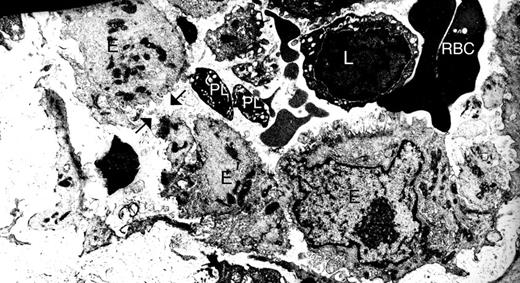

For this study, we aimed to examine platelets in a context where increased vasculature permeability and inflammation are present. Gaps are found between endothelial cells in the synovial vasculature from patients with RA,10 and our electron microscopic analyses of synovial tissues from these patients also reveal platelets in the vicinity of these gaps10 (Figure 1). Thus, autoimmune inflammatory arthritis appeared to us as an ideal condition to investigate the role of platelets in the context of enhanced vasculature permeability.

Gaps are present between endothelial cells in the synovium vasculature from patients with RA. Synovium from RA patients was scrutinized by electron microscopy. Black arrows indicate one gap between endothelial cells. E indicates endothelial cells; PL, platelets; L, lymphocytes; and RBC, red blood cells. Original magnification ×48 400.

Platelets play a crucial role in hemostasis by preserving the integrity of the vasculature.2 Therefore, how could the platelets contribute to the increased joint permeability during arthritis? Given its abundance in platelets, serotonin (5-hydroxytryptamine) was initially detected in blood,25 and studies have examined its function(s) in vascular permeability26,27 and joint edema.17 A pioneering electron microscopic investigation showed that local injection of serotonin in the cremaster muscle induced the formation of gaps, 0.1 to 0.8 μm in width, between endothelial cells.26 Interestingly, the authors frequently observed the presence of platelets, sometimes bridging these gap, sometimes plugging them, and also noticed disintegrating platelets near these gaps.26 Given the striking similarities between the gaps observed in RA synovium10 (Figure 1A) and those observed after serotonin injection,26 we hypothesized that platelets may promote the gap formation via serotonin.